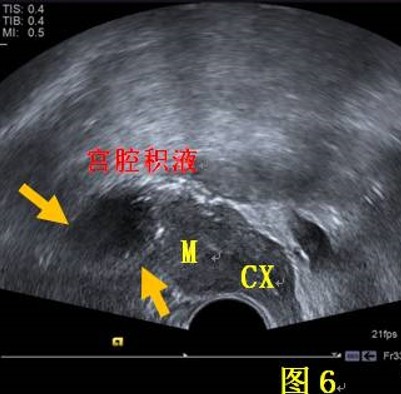

03、宮腔積液是怎么回事?怎么辦?

宮腔積液又稱子宮積液,宮腔積液可能是生理性的,也可能性是病理性的。

病理性的宮腔積液常見的原因是炎性疾病,但是也不能排除婦科腫瘤。絕經(jīng)后女性,宮腔積液多為病理性。

絕經(jīng)后,女性卵巢功能下降,體內(nèi)激素水平降低,宮頸分泌粘液功能減低,陰道自凈能力下降,內(nèi)膜萎縮,容易導(dǎo)致陰道病菌逆行并感染;宮頸萎縮、粘連,宮腔內(nèi)分泌物難以排除,進(jìn)而形成了宮腔積液。

對于我們?nèi)橄侔﹥?nèi)分泌治療期間的患者來說,抑制雌激素的過程也有可能增加宮腔積液的發(fā)生,但是,具體積液的性質(zhì)需要結(jié)合其他的檢查,比如宮腔鏡。

宮腔鏡檢查不僅能明確積液性質(zhì),也能清楚的明確宮腔內(nèi)部情況,并做到定點(diǎn)活檢,避免漏診,甚至可以協(xié)助治療。